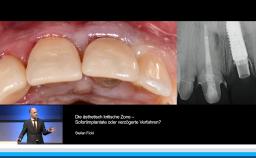

Prof. Buser berichtet in dieser Präsentation, die im Rahmen des Deutschen ITI Kongresses in Dresden im Jahr 2015 gehalten wurde. Langzeiterfolg von Implantaten über 20 Jahre, über den optimalen Implantation und Belastungszeitpunkt. Zunächst erläutert er die gewandelte Altersstruktur der Implantatpatienten und definiert die primären und sekundären Behandlungsziele in der Implantologie. Ein zentraler Aspekt der Präsentation stellt die Wahl des idealen Implantationszeitpunktes nach Extraktion mit Focus auf die verzögerte Sofortimplantation in Verbindung mit GBR dar, die auch mit einem informativen OP Video unterlegt ist. Er setzt sich kritisch mit dem Konzept der Sofortimplantologie auseinander und stellt die Ergebnisse der letzten ITI Konsensuskonferenz dar. Er definiert die Belastungszeitpunkte auf der Basis der ITI Konsensuskonferenz. In einem zweiten Schritt wird die Planung der Belastung in den Zusammenhang mit der Verlaufsbeurteilung der Implantatstabilität mittels ISQ Messung gestellt. Am Beispiel des Sinuslift mit primärer Implantation wird abschließend das Konzept eines flexiblen Belastungszeitpunktes auf Basis der ISQ Messung diskutiert.

• die Wahl des idealen Implantationszeitpunktes in der ästhetisch kritischen Zone verstehen

• die GBR als Technik zur verzögerten Sofortimplantation in der Praxis anwenden können